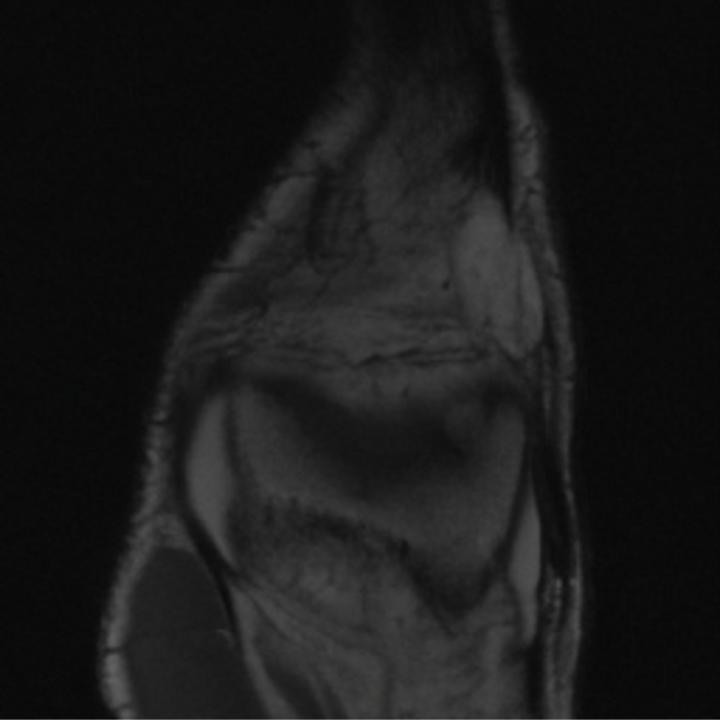

Notably, X-Diffusion achieves sota dB for a few input slices while baselines require more than 60 input slices to achieve similar performance (Figure 7). The margin is more than 12 dB PSNR for the 1-slice input in both the BRATS and the UK Biobank benchmarks (see Table 1 and Figure 6). For reference, two randomly sampled MRIs from the UK Biobank would have a PSNR of 15.95 dB 0.36 (on 4800 randomly sampled examples). The slices from 3D reconstructed volumes at varying depths and axis of rotation visually match the ground truths (see Figures 5 and Figure 4). We also plot the error map (Figure 4) of such X-Diffusion generations to highlight the differences with the ground truth MRIs.

One way to test the generalization capability of the trained X-Diffusion is to test it on a completely different domain from an MRI dataset not seen during training. We report the single-slice results on the test set of knees from NYU fastMRI [33, 80], using the X-Diffusion trained on the BRATS brain MRIs. The test PSNR result is 34.17 and an example is shown in Figure 8. It shows how successfully X-Diffusion can generate knee MRIs (out-of-domain) despite being trained on brains.